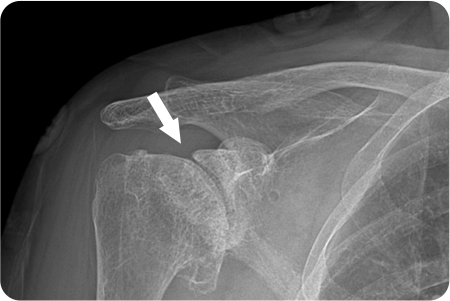

2

어깨 관절염

인공관절치환술

관절염으로 닳아버린 손상된 연골과 뼈를

정밀하게 절제합니다. 환자의 상태에 따라

전치환술/반치환술 중 선택하여 시행

합니다.